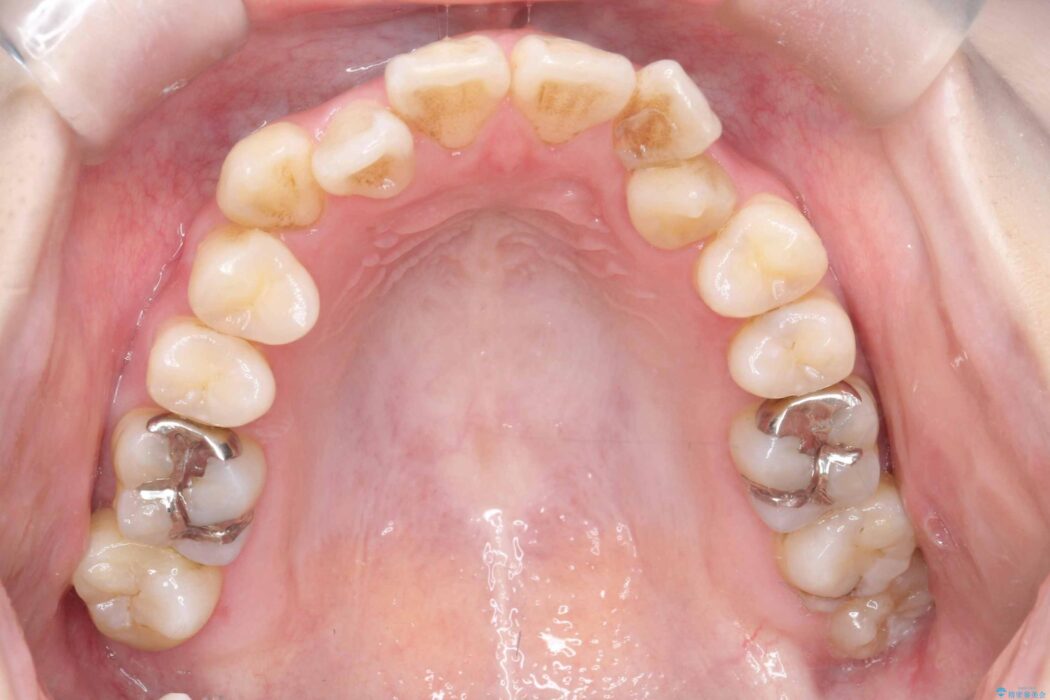

精密検査の結果、上顎左右4番および下顎左右5番の計4本を抜歯し、目立ちにくいクリア装置にて治療を行いました。

また、虫歯があったので、矯正開始前に虫歯治療を行っております。

気になっていたガタつきや開咬が改善され、見た目だけでなく咬み合わせの機能面も大きく向上し、大変ご満足いただけました。